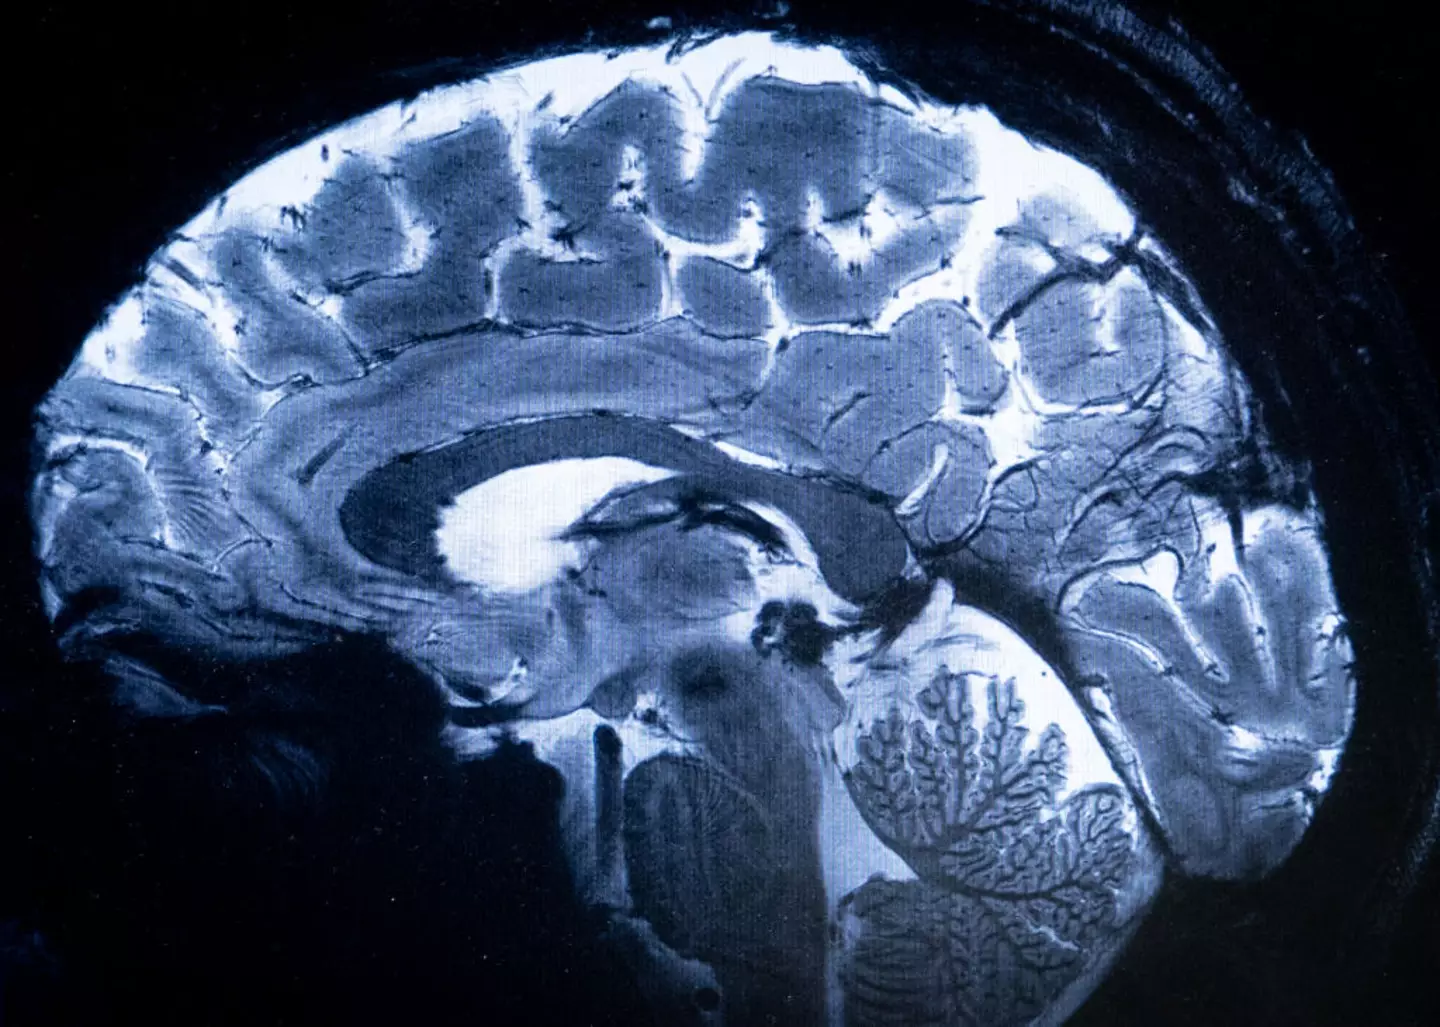

However, it's less shocking when you factor in that the idea that a brain's frontal and prefrontal cortex - which is responsible for our impulse control and emotional regulation - doesn't finish developing until the age of 25, which is a perfect excuse to write off any embarrassing actions during the early years of adulthood.

Things don't get much better once we pass our peak either, with Mindea adding that the brain 'gradually atrophies or shrinks' once we pass the age of 65.